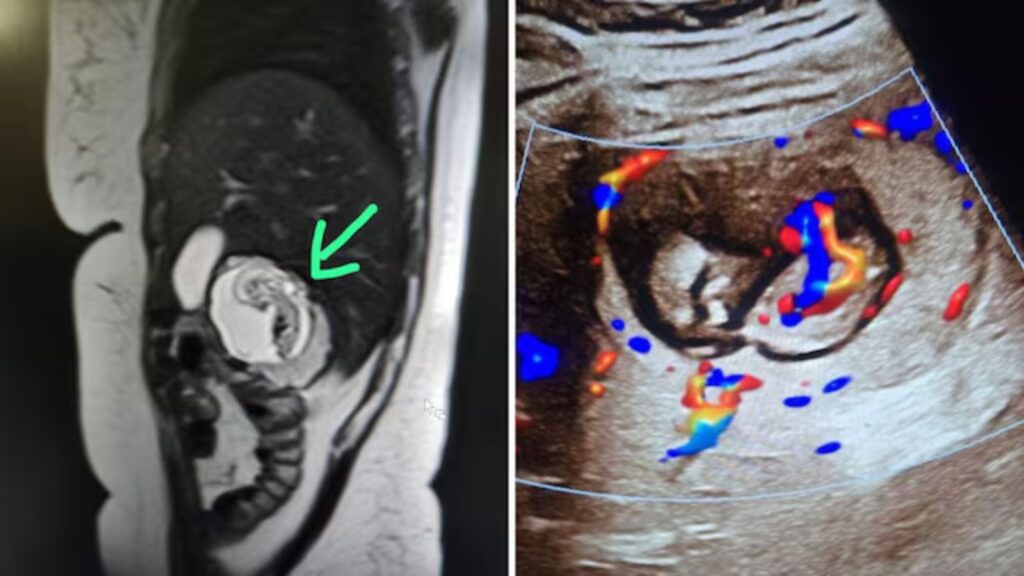

ಸ್ಕ್ಯಾನ್ನ ಫಲಿತಾಂಶಗಳು ವೈದ್ಯರನ್ನು ದಿಗ್ಭ್ರಮೆಗೊಳಿಸಿದವು. ಯಕೃತ್ತಿನ ಬಲ ಹಾಲೆಯೊಳಗೆ 12 ವಾರಗಳ ಭ್ರೂಣವು ರೂಪುಗೊಂಡಿತ್ತು. ಗರ್ಭಾವಸ್ಥೆಯ ಚೀಲವು ಯಕೃತ್ತಿನ ಪ್ಯಾರೆಂಚೈಮಲ್ ಅಂಗಾಂಶದೊಳಗೆ ಆಳವಾಗಿ ಕೂಡಿತ್ತು. ಭ್ರೂಣವು ಸಕ್ರಿಯ ಹೃದಯ ಬಡಿತಗಳನ್ನು ತೋರಿಸಿದ್ದು, ಇದು ಜೀವಂತವಾಗಿರುವುದನ್ನು ದೃಢಪಡಿಸಿತ್ತು. ಆಶ್ಚರ್ಯಕರವಾಗಿ, ಗರ್ಭಾಶಯವು ಸಂಪೂರ್ಣವಾಗಿ ಖಾಲಿಯಾಗಿತ್ತು. ಡಾ. ಗುಪ್ತಾ ಅವರು, “ನನ್ನ ಕಣ್ಣುಗಳನ್ನು ನಂಬಲು ಸಾಧ್ಯವಾಗಲಿಲ್ಲ. ಯಕೃತ್ತಿನಲ್ಲಿ ಭ್ರೂಣವಿರುವುದನ್ನು ನೋಡಿದಾಗ, ಇದು ಭಾರತದ ಮೊದಲ ಇಂಟ್ರಾಹೆಪಾಟಿಕ್ ಎಕ್ಟೋಪಿಕ್ ಗರ್ಭಧಾರಣೆಯಾಗಿರಬಹುದು ಎಂದು ತಿಳಿದು ಆಶ್ಚರ್ಯವಾಯಿತು,” ಎಂದು ಹೇಳಿದ್ದಾರೆ.

ಇಂಟ್ರಾಹೆಪಾಟಿಕ್ ಎಕ್ಟೋಪಿಕ್ ಗರ್ಭಧಾರಣೆಯು ಅತ್ಯಂತ ಅಪರೂಪದ ಮತ್ತು ಅಪಾಯಕಾರಿ ಸ್ಥಿತಿಯಾಗಿದೆ. ಯಕೃತ್ತಿನ ರಕ್ತನಾಳಗಳು ಗರ್ಭಾವಸ್ಥೆಯ ಚೀಲಕ್ಕೆ ಪೋಷಕಾಂಶಗಳನ್ನು ಒದಗಿಸುತ್ತವೆ. ಆದರೆ ಈ ಸ್ಥಿತಿಯು ತಾಯಿಯ ಆರೋಗ್ಯಕ್ಕೆ ಗಂಭೀರ ಅಪಾಯವನ್ನುಂಟುಮಾಡಬಹುದು. ಈ ರೀತಿಯ ಗರ್ಭಧಾರಣೆಯು ಸಾಮಾನ್ಯವಾಗಿ ಗರ್ಭಾಶಯದ ಹೊರಗಿನ ಇತರ ಸ್ಥಳಗಳಾದ ಫಲೋಪಿಯನ್ ಟ್ಯೂಬ್ನಲ್ಲಿ ಕಂಡುಬಂದರೂ, ಯಕೃತ್ತಿನೊಳಗೆ ಇದು ಅತ್ಯಂತ ಅಸಾಧಾರಣವಾಗಿದೆ.

ಡಾ. ಗುಪ್ತಾ ಅವರ ಪ್ರಕಾರ, ಎಂಆರ್ಐ ಸ್ಕ್ಯಾನಿಂಗ್ನ ಸುಧಾರಿತ ತಂತ್ರಜ್ಞಾನವು ಈ ಅಪರೂಪದ ಸ್ಥಿತಿಯನ್ನು ಗುರುತಿಸುವಲ್ಲಿ ನಿರ್ಣಾಯಕ ಪಾತ್ರ ವಹಿಸಿತ್ತು. “ಅಲ್ಟ್ರಾಸೌಂಡ್ಗಿಂತ ಎಂಆರ್ಐ ಹೆಚ್ಚಿನ ವಿವರಗಳನ್ನು ಒದಗಿಸಿತ್ತು. ಇದು ಯಕೃತ್ತಿನ ಒಳಗಿನ ಭ್ರೂಣದ ಸ್ಥಿತಿಯನ್ನು ಸ್ಪಷ್ಟವಾಗಿ ತೋರಿಸಿತ್ತು,” ಎಂದು ಅವರು ವಿವರಿಸಿದ್ದಾರೆ.